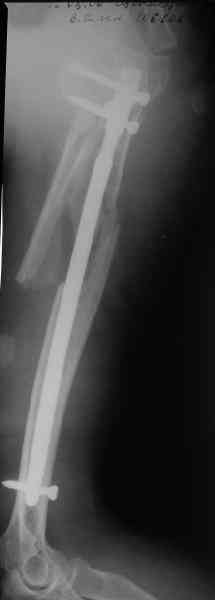

Здесь нет необходимости в серкляже. Вмешиваться на промежуточных отломках приходится, если есть угроза перфорации кожи, или промежуточный отломок попал в фасцию, как пуговица в петлю. В приложении сегментарный оскольчатый перелом плеча в проксимальном отделе, фиксированный больщеберцовым стержнем. Как видите, обошлось без серкляжа. Функция полная.